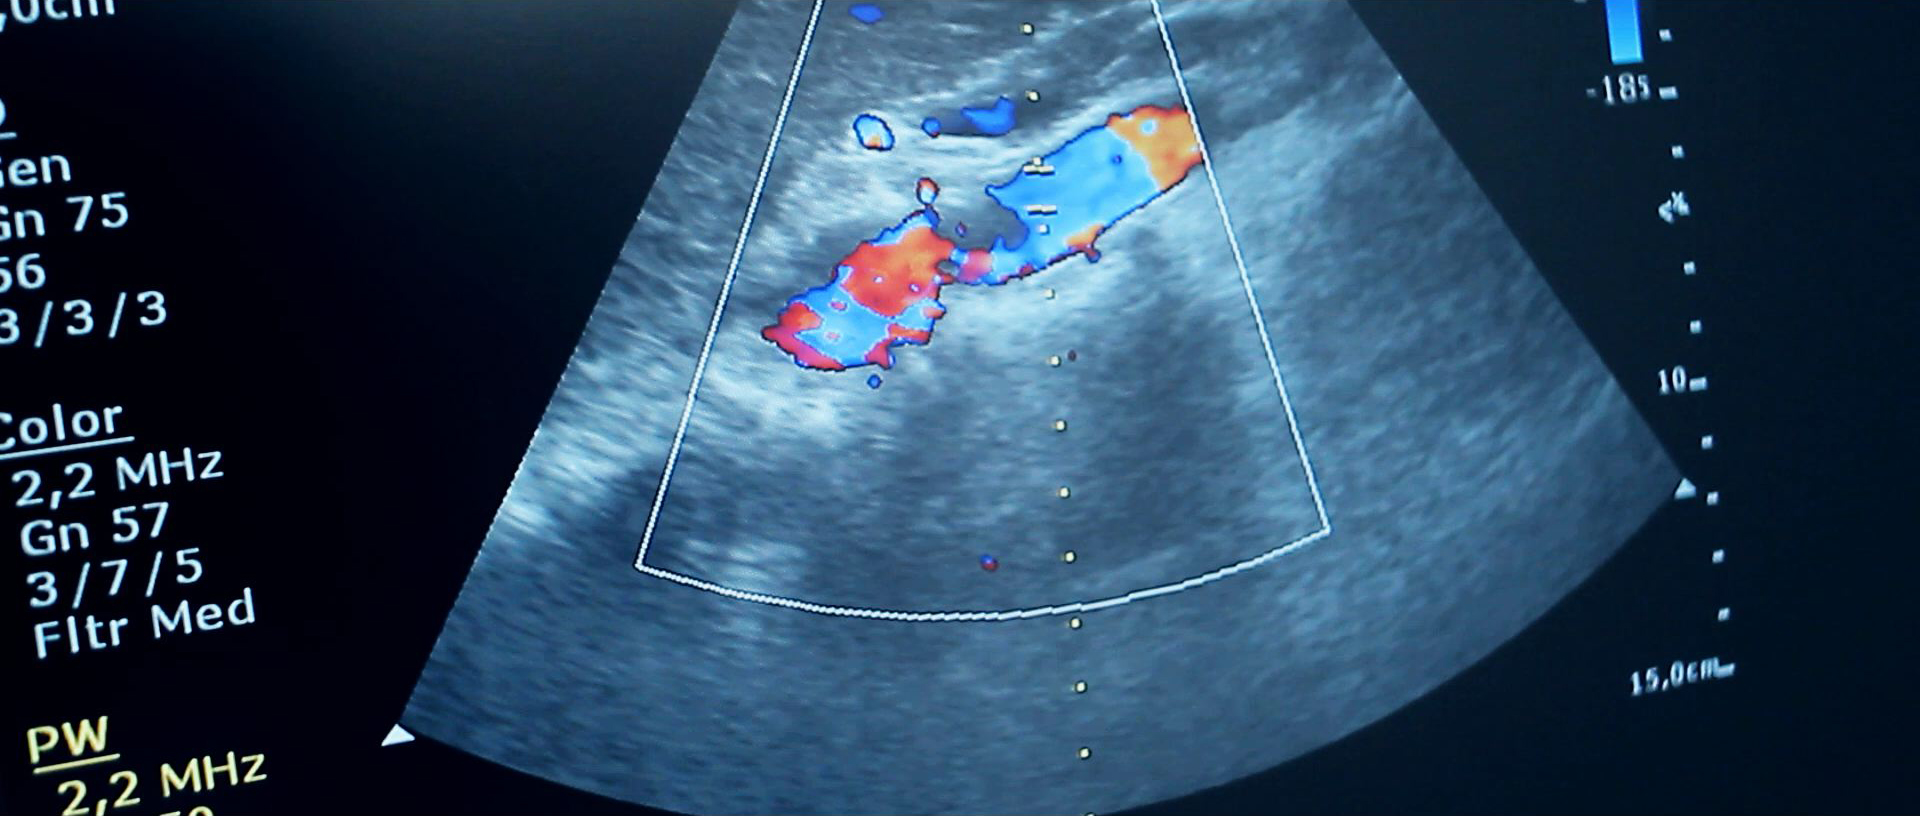

Color Doppler abdomena je ultrazvučna tehnika pregleda kojom se pregledavaju krvne žile unutar trbušne šupljine te se procjenjuje prokrvljenost unutrašnjih organa. Sama tehnika color ili obojenog Dopplera zasnovana je na fizikalnom zakonu poznatom pod imenom Dopplerov efekt a koji nam opisuje odnose između objekta koji se kreće i ultrazvučnih valova koji ga prate u tom kretanju. Na osnovu tih parametara možemo računati volumene i brzine protoka krvi kroz ispitivane krvne žile i organe. Ispitivanje renalnih arterija sastavni je dio dijagnostičke obrade svih pacijenata koji imaju povišen arterijski tlak. Procjena ateroskleroze, odnosno suženja arterija, kao i praćenje dinamike razvoja bolesti, te okrivanje abdominalne aneurizme (proširenja krvne žile) kao izrazito opasnog stanja moguće je pomoću color Dopplera.

Procjena venske cirkulacije odnosno povrata krvi ka srcu putem vena moguća je također ovom tehnikom. Nadalje se color Dopplerom dobivaju iznimno važne informacije o prokrvljenosti tumora i drugih patoloških procesa, kao što je ciroza jetara, unutar trbušne šupljine. Evaluacija i kontinuirano praćenje prokrvljenosti transplantiranih organa (bubrega, jetara itd.) vrlo elegantno se radi uz pomoć color Dopplera. Kao i kod ultrazvučnog pregleda abdomena rezultati jako ovise o kvaliteti ultrazvučnog aparata pomoću kojeg se radi color Doppler abdomena, kao i o iskustvu i umijeću liječnika koji vrši pregled.